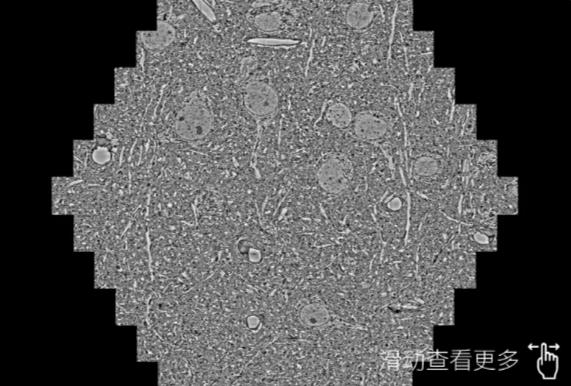

鼠脑切片。左图使用金昌蔡司金昌扫描电镜MultiSEM706对165μmx143pm面积区域成像,耗时仅需1.5秒。右图为鼠脑切片中30μm区域放大效果。样品由芝加哥大学B.Kasthuri提供。

使用蔡司高速金昌扫描电镜MultiSEM对1mm²人脑皮层组织进行高分辨成像,并对其中的各种细胞结构进行三维重构分析。左图展示了2x3mm²组织平面中锥体神经元的三维重构效果。右图显示了局部体积神经元三维重构。图像由哈佛大学chtman实验室提供,渲染图由D. Berger 制作。